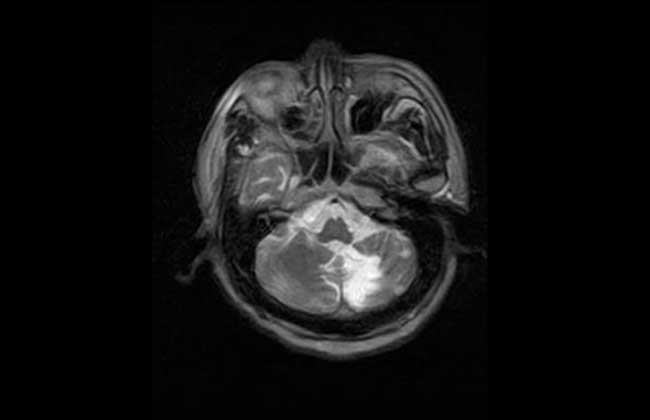

企鹅病就是指遗传性小脑性共济失调,是所有报道的共济失调中最多的一种,发病机理未明,病变主要累及小脑,但脊髓及颅神经也可部分受累,患者行走如企鹅般摇摇晃晃,遗传方式为常染色体显性遗传,男女发病率无明显差异。